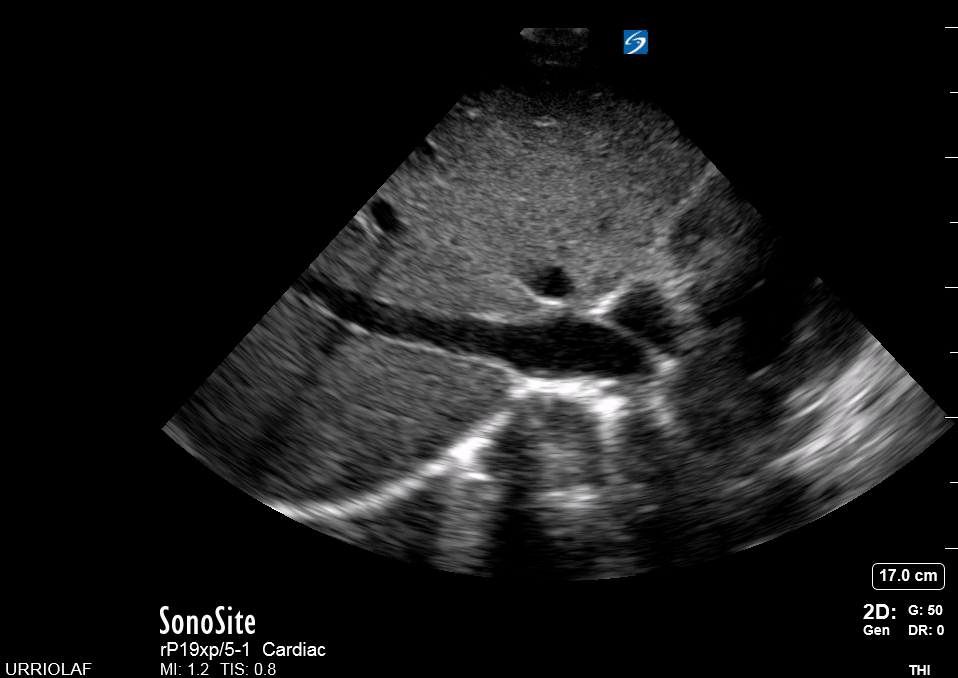

SUBXIPHOID VIEW

This is the standard window taught in FAST and might be the only one available during cardiopulmonary resuscitation (CPR). This view uses the liver as an acoustic window. To obtain good visualization is essential to handle the probe almost parallel to the anterior abdominal wall, trying to place it under the xiphoid process, pointing to the left shoulder. A deep inspiration or half inspiration can be useful to bring the heart closer to the probe and improve visualisation.

Remember that in the cardiac preset, the screen marking is on the right side. As a result, and unlike the FAST exam, the probe marking points towards the patient’s left. This view is used mainly to look for pericardial fluid, but it also provides information about ventricle size, chamber relationship and valvular abnormalities.